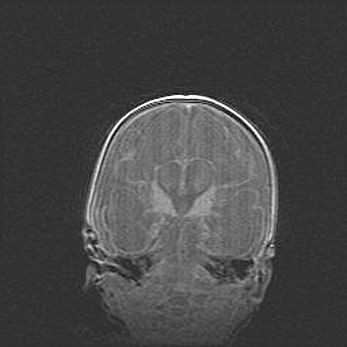

Ниже представлена  галерея МРТ снимков, полученных с применением LMT неонатальных матричных РЧ катушек. Также каждая группа МРТ снимков сопровождается информацией о пациенте (диагноз, возраст, вес, пол, срок гестации) и краткой сопроводительной расшифровкой диагноза.

Наружная гидроцефалия с возможной атрофией височных областей.

Возраст: 28 дней

Вес: 3670 г

Пол: мужской

Окружность головы: 38 см

Срок гестации: 40 недель

Гидроцефалия головного мозга у новорожденных – это заболевание, которое характеризуется скоплением избыточного количества спинномозговой жидкости в желудочковой системе головного мозга в результате затруднения её перемещения от места выработки к месту поглощения в кровеносную систему или вследствие нарушения абсорбции. При открытой наружной форме гидроцефалии у новорожденных расширяются и переполняются субарахноидные пространства.

При нормотензивных  формах,  которые,  как  правило,  являются  следствием  перенесенных ишемических  повреждений  паренхимы  мозга,  возможно  сочетание микроцефалии  с нормотензивной гидроцефалией. В основе данных изменений лежит атрофия больших полушарий с преимущественной  локализацией  в  лобно-височных  областях.